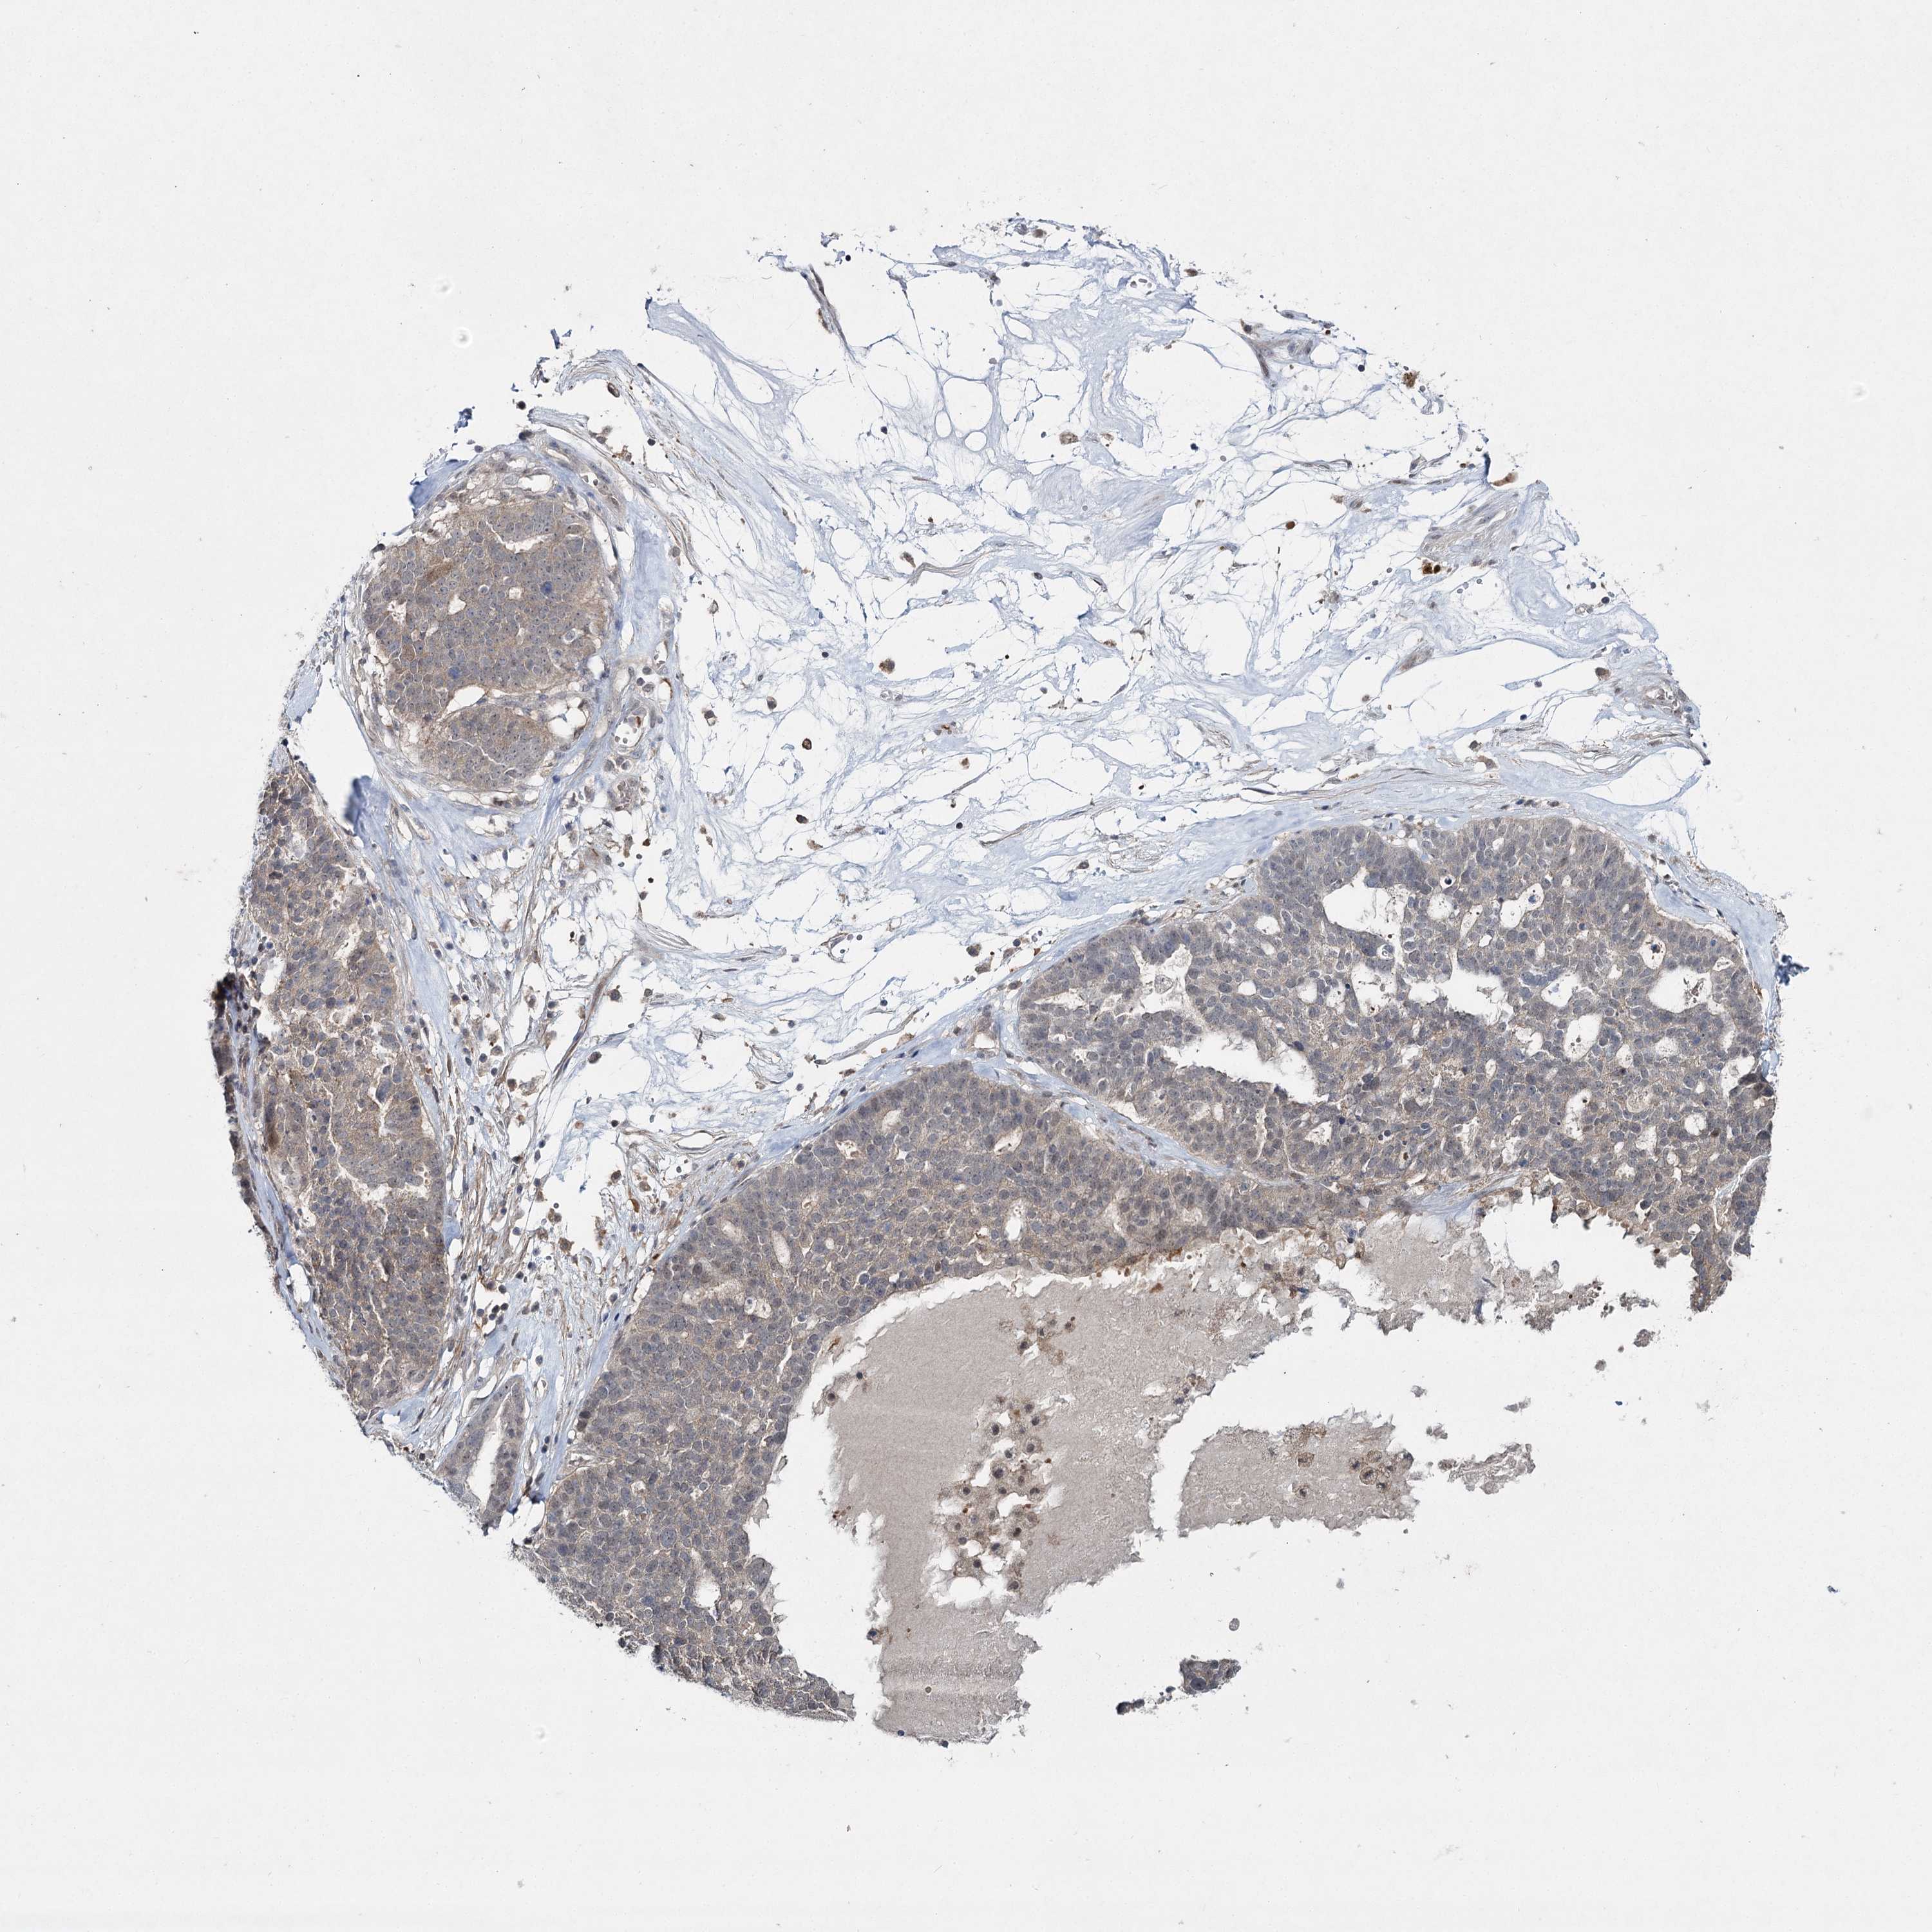

OVARIAN CANCER - Protein expressioni

A mouse-over function shows sample information and annotation data. Click on an image to view it in a full screen mode. Samples can be filtered based on level of antibody staining by selecting one or several of the following categories: high, medium, low and not detected. The assay and annotation is described here.

Note that samples used for immunohistochemistry by the Human Protein Atlas do not correspond to samples in the TCGA dataset.

Antibody stainingi

Antibody staining in the annotated cell types in the current human tissue is reported as not detected, low, medium, or high, based on conventional immunohistochemistry profiling in selected tissues. This score is based on the combination of the staining intensity and fraction of stained cells.

Each image is clickable and will lead to virtual microscopy that enables deeper exploration of all samples and also displays staining intensity scores, fraction scores and subcellular localization as well as patient and tissue information for each sample.

Antibody HPA038084

Cystadenocarcinoma, serous, NOS

Carcinoma, endometroid

Cystadenocarcinoma, mucinous, NOS

Carcinoma, NOS